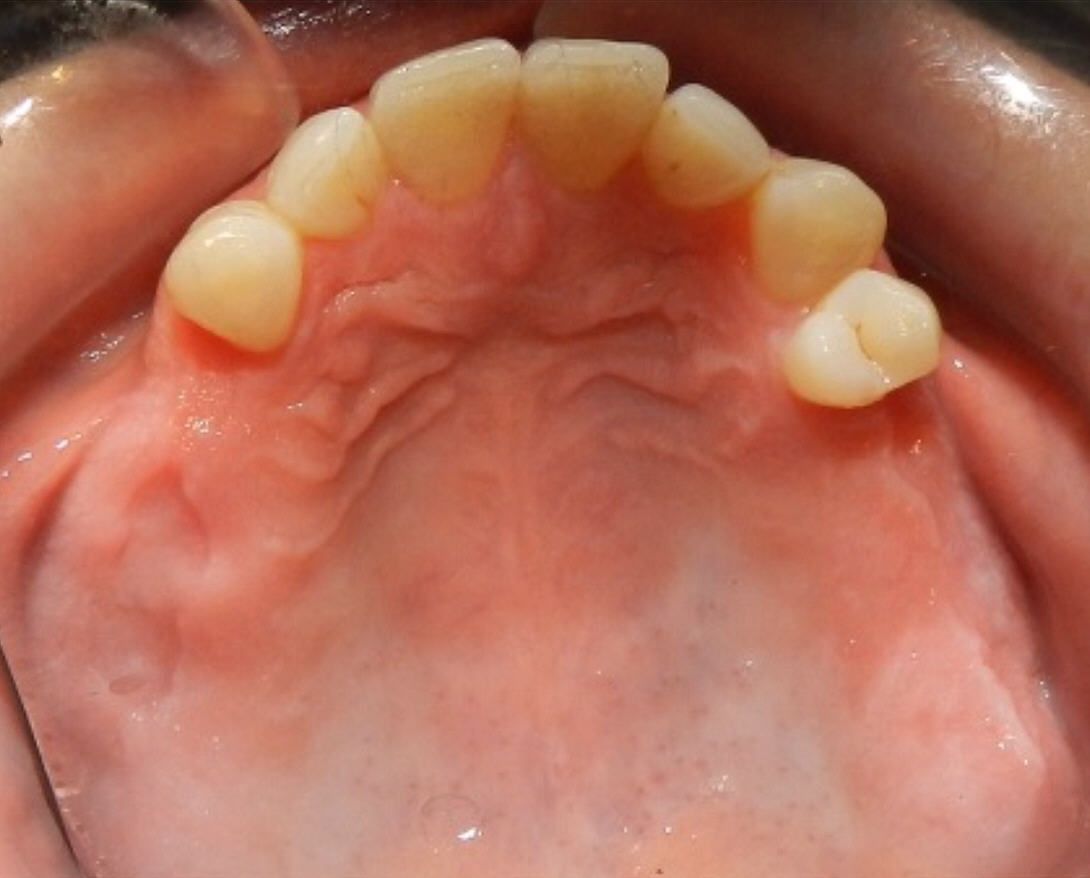

Before